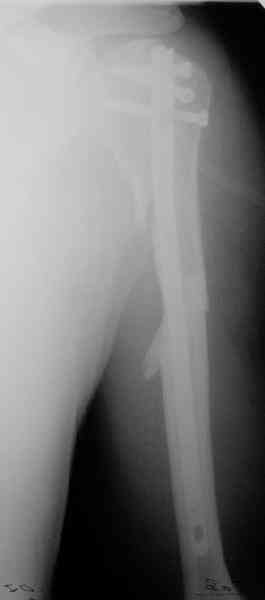

Дорогие коллеги,Мужчина 44 л. упал с крыши дачи 6 августа. Картинки в приложении. Лет 5 назад нде-то оперирован по поводу привычного вывихв этого же плеча.После операции не вывихивал до этой травмы.Как тут лечить? Есть ли шансы на закрытое вправление? Чем лучше фиксировать? Какие меры принять с учетом бывшего и нынешнего вывиха? Заранее спасибо. Dear colleagues, A male 44 y.o. admitted to our unit. Injured at Aug. 6 - fall from 3 m. Images attached. Five years ago was operated somewhere else for recurrent dislocation of thу same shoulder, no data what was done. What would be optimal treatment option? Any chance of closed reduction? What should be done to address the current and past dislocations? THX.

I would recommend an initial attempted closed reduction in the OR with fluoroscopy. It is important that this is done in a controlled fashion to make sure you are not further displacing the head and leaving it behind. If

you can get it reduced then you will have a much better ability to understand the fracture and possible glenoid involvement. I think regardless

of getting the humeral head reduced this fracture should be managed operatively with plate fixation of the tuberosity fragment and a combination of lag screw and plate fixation of the proximal shaft extension. My concern is that treating it conservatively after closed reduction will lead to issues of instability and malunion given the size of the tuberosity fragment and past history.

I would also not be surprised if there was some glenoid issues related to the prior instability. It is difficult to tell on the provided xrays. Either a CT scan or an Axillary view should be done to assess this prior to definitive surgery.

This is an anterior fracture/dislocation with shaft extension-no chance for closed reduction-probably contraindicated, especially since the injury is now 19 days old. We do these supine on a radiolucent table with an arm board extension-you now have an unobstructed radiographic view of the entire upper extremity both AP and lateral with excellent axillary views of the glenohumeral joint to assess your reduction and screw placement. This is the perfect indication for a locking plate via the traditional deltopectoral approach. Use the biceps tendon to stay anatomically oriented during the approach and be sure to check the rotation post plate application. In general, we have not performed any soft tissue stabilization procedures during the fixation, may stay away from external rotation past neutral during rehab and early motion protocol. This one should do fine.